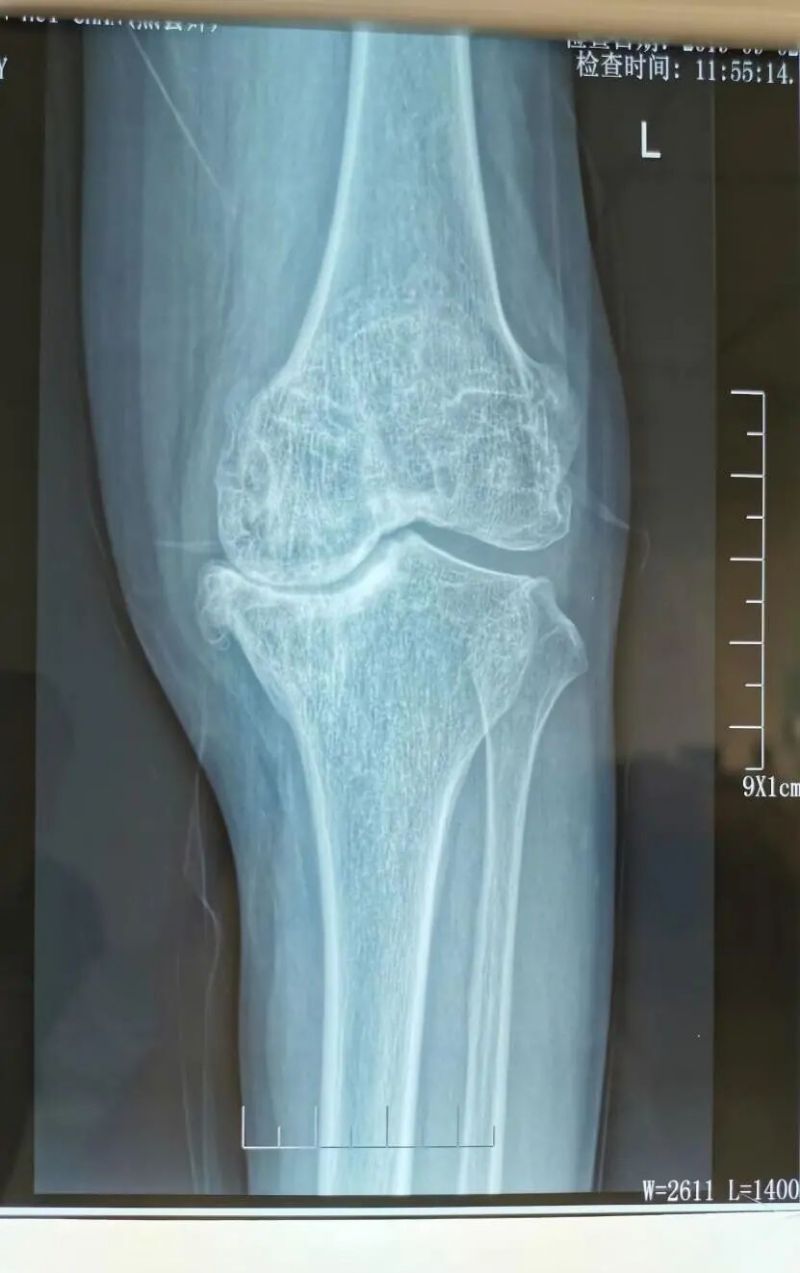

影像學(xué)檢查是診斷的重要手段。X線檢查就像給關(guān)節(jié)拍了一張“照片”,能夠清晰地顯示關(guān)節(jié)間隙變窄、骨質(zhì)增生、軟骨下骨硬化等典型表現(xiàn)。而MRI檢查則更像是一部“高清攝像機”,能更清晰地觀察關(guān)節(jié)軟骨、半月板、滑膜等軟組織的病變情況,為醫(yī)生提供更準(zhǔn)確的診斷依據(jù)。